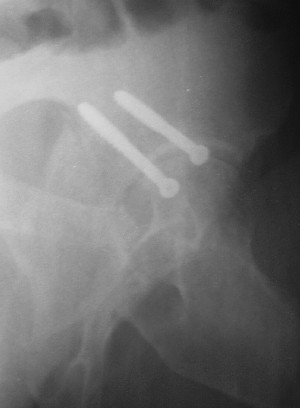

Больной 18 мая 2003 года в автоаварии получил перелом левой вертлужной впадины, вывих бедра. Госпитализирован в один из стационаров области.Вывих вправлен. В последствии бедро вывихивалось еще дважды. На консультацию был представлен снимок от 19.05.03г., больной переведен к нам 3.06.03г. Снимок при поступлении - перелом впадины, задне-верхний вывих бедра. 05.06.2003 г. выполнено открытое вправление вывиха левого бедра и остеосинтез стенки вертлужной впадины двумя винтами. Послеоперационный период без осложнений. Объем движений в левом тазобедренном суставе восстановился полностью. Выписан на амбулаторное лечение в удовлетворительном состоянии с рекомендациями 3 месяца ходить на костылях без нагрузки на оперированную конечность. На контрольных рентгенограммах левого тазобедренного сустава 13.10.2003 г. - признаки консолидации перелома; плотность, форма головки и состояние суставных поверхностей удовлетворительные. Разрешена дозированная осевая нагрузка, на конечность с использованием дополнительной опоры. 19.12.2003 г. больной обратился с жалобами на боли в левом тазобедренном суставе. На рентгенограммах левого тазобедренного сустава 19.12.2003 г., 20.02.04г. - асептичекий некроз головки бедра. 5.04.04г. - эндопротез. Сейчас ходит без трости, не хромает. Особенность эндопротезирования - при удалении винтов прослежена линия перелома заднего края впадины и предложено установить чашку несколько меньшего диаметра, чтобы она была покрыта несломанной частью.